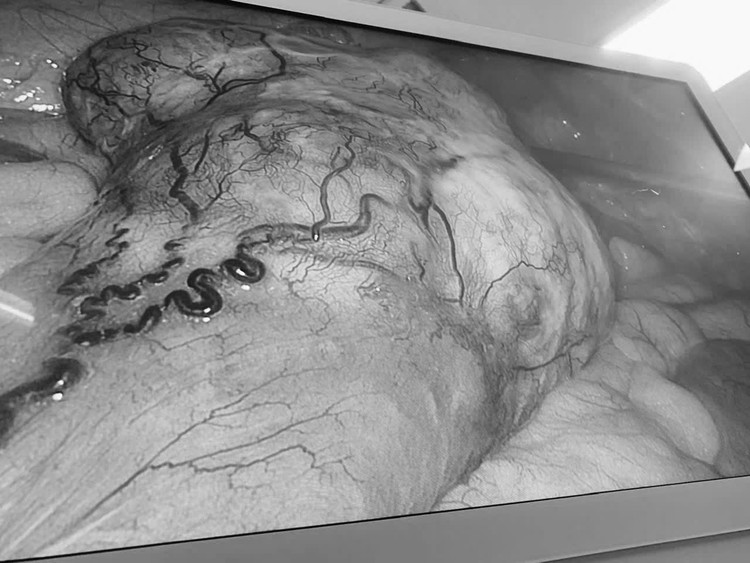

Hình ảnh khối u được quan sát rõ qua nội soi trong quá trình phẫu thuật, giúp bác sĩ đánh giá chính xác vị trí và mức độ tổn thương. Ảnh BV

Theo ThS.BS.CKI Trần Nhật Phi, phẫu thuật viên trực tiếp thực hiện ca mổ cho bệnh nhân N.T.N. chia sẻ: “Việc phẫu thuật cho bệnh nhân mang đồng thời hai khối u ở hai vị trí khác nhau là một thách thức lớn. Thời gian mổ kéo dài, nguy cơ biến chứng tăng cao và luôn tiềm ẩn khả năng phải chuyển sang phẫu thuật mở nếu không kiểm soát tốt các tình huống phát sinh trong quá trình can thiệp”.

Theo bác sĩ, những khó khăn chính đặt ra trong ca phẫu thuật bao gồm việc phải phẫu tích đồng thời ở hai vùng giải phẫu khác nhau, vừa đảm bảo nguyên tắc ung thư học trong điều trị ung thư đại tràng, vừa kiểm soát tốt tình trạng chảy máu, bảo tồn tối đa các cấu trúc lành, đồng thời đảm bảo an toàn gây mê trong suốt thời gian phẫu thuật kéo dài.